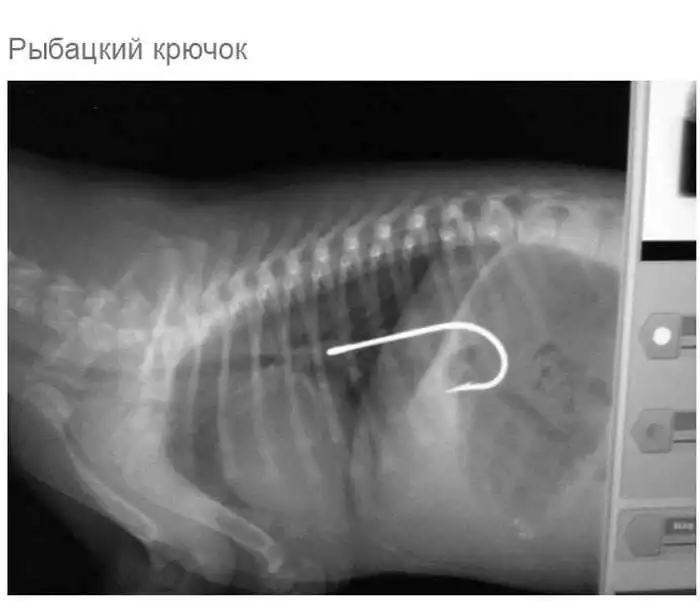

Что может оказаться в желудке собаки

Думаю, всем собачникам известно, что порой у собак бывают такие заскоки, когда они в прямом смысле слова жрут все подряд.